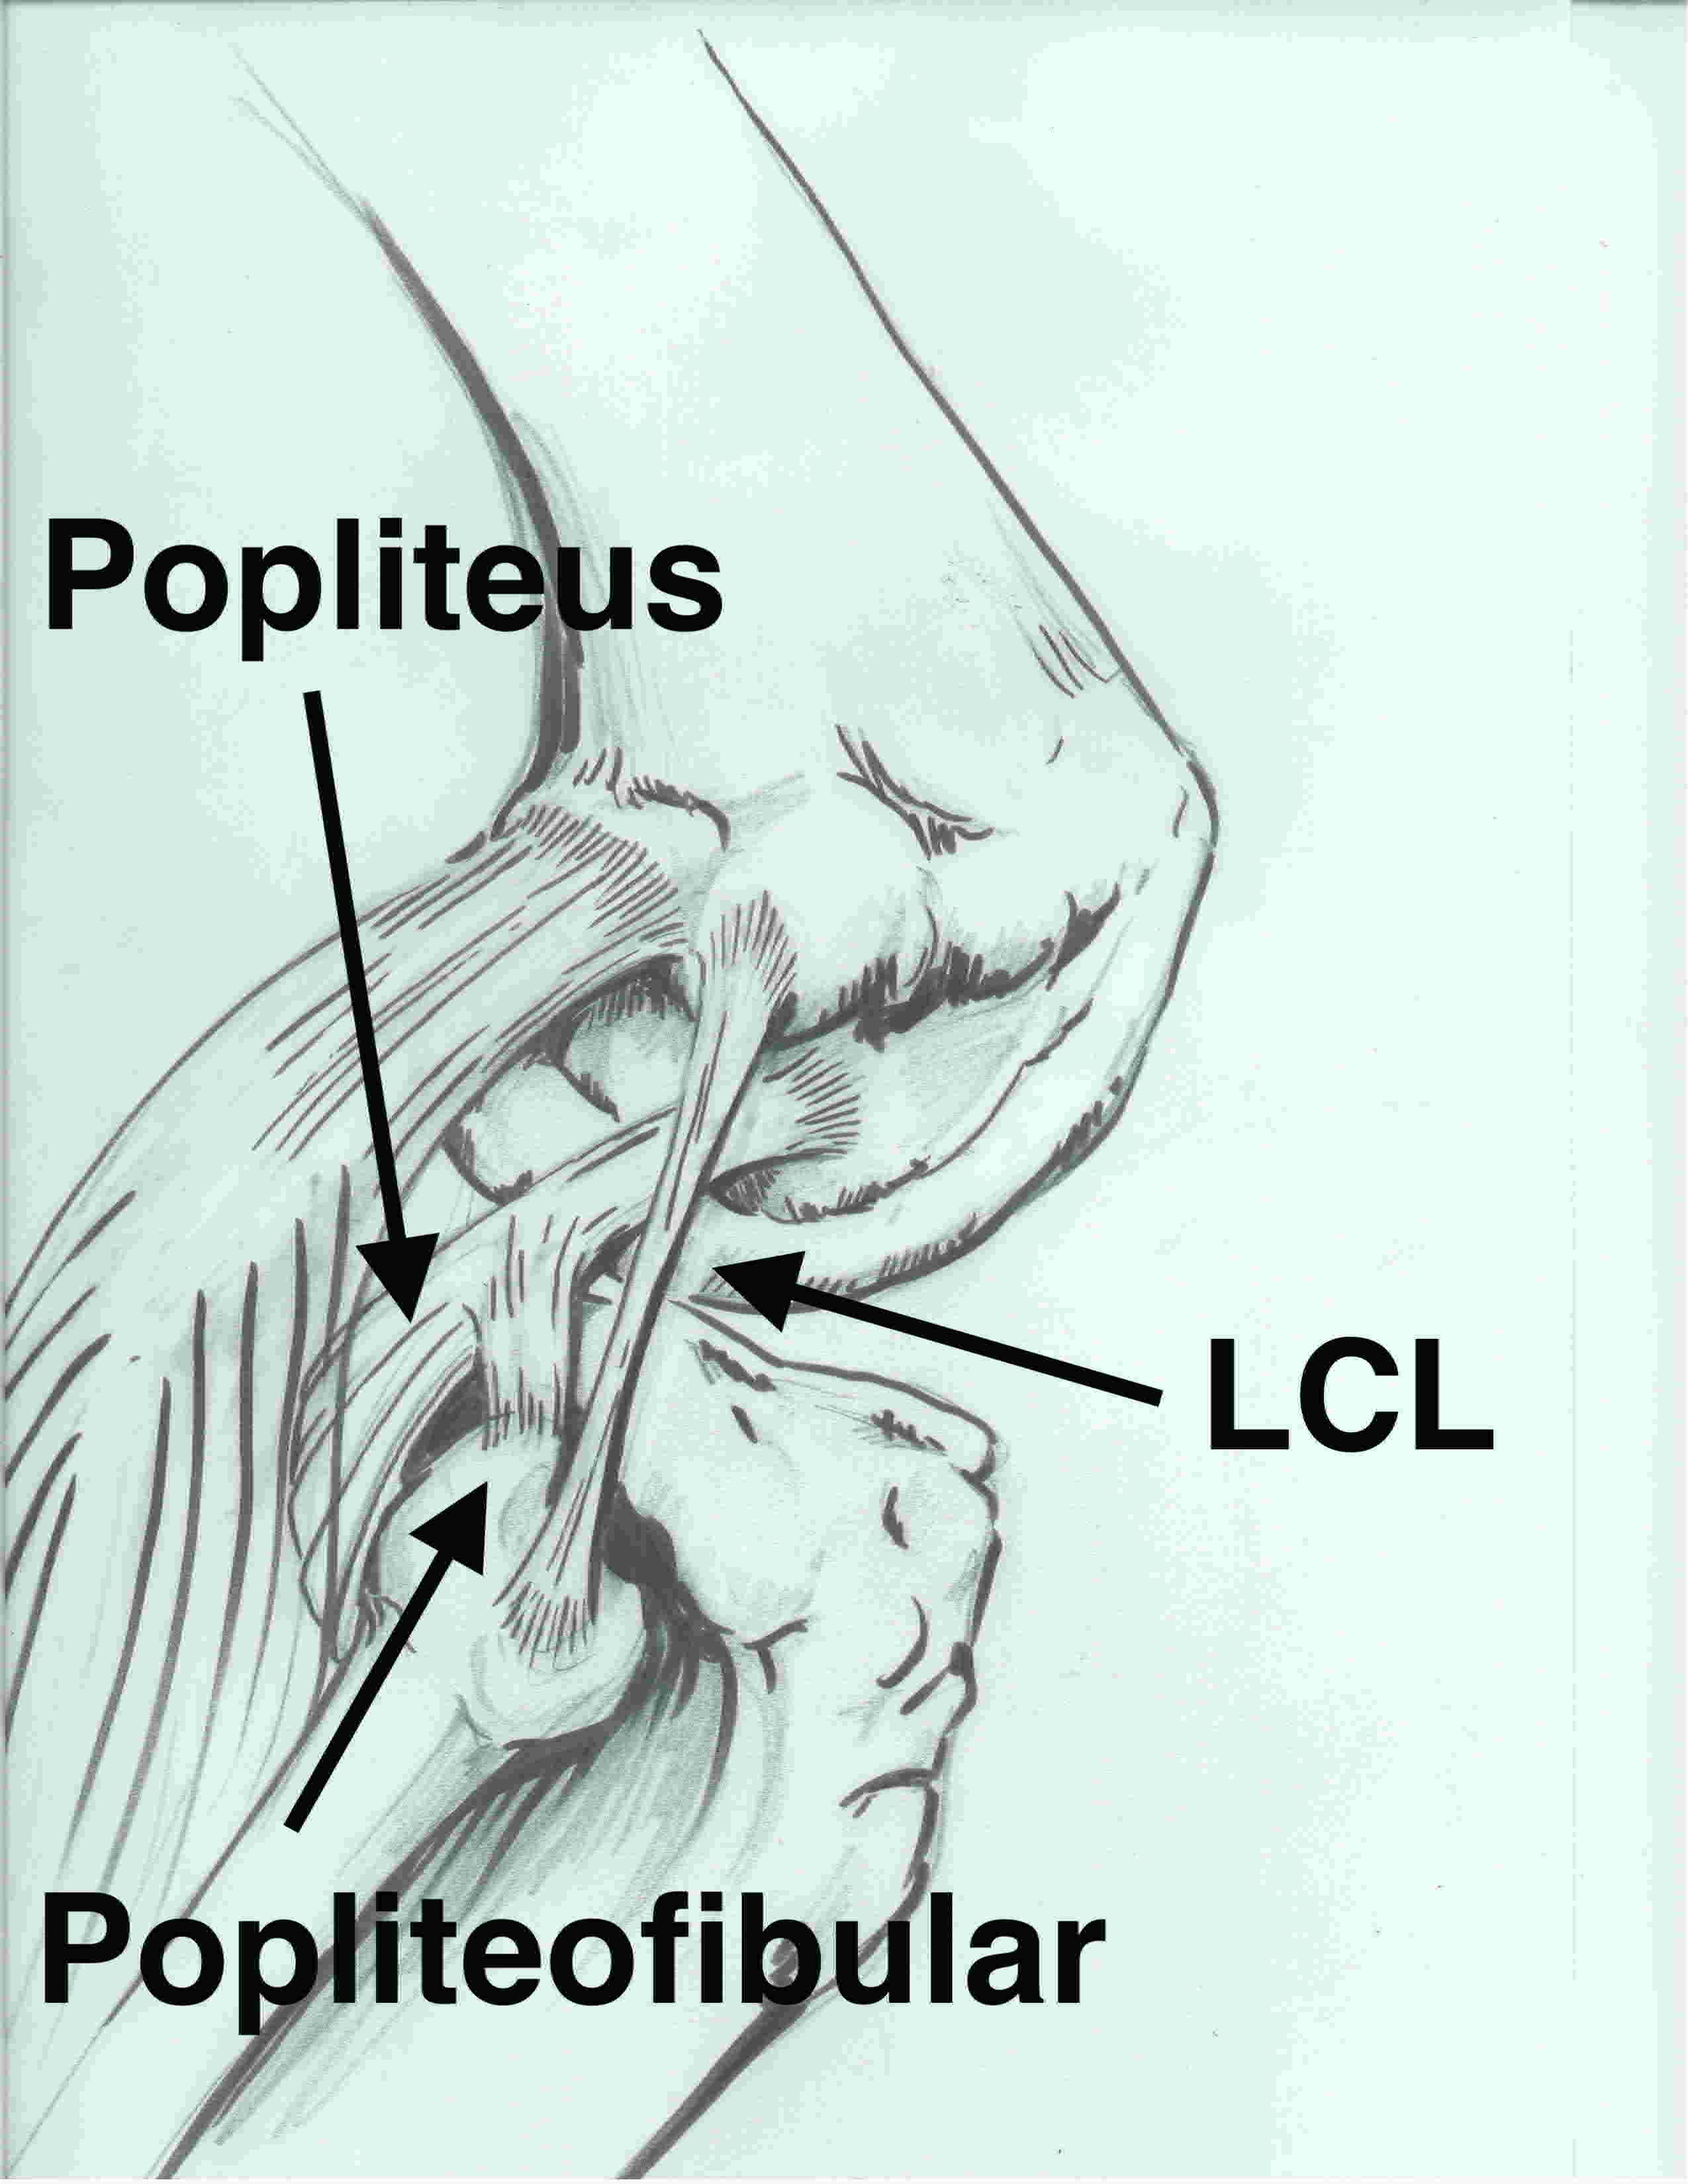

3 primary stabilizers (plus posterolateral capsule)

LCL / Popliteus / Popliteofibular ligament

1. Lateral collateral ligament

2. Popliteus tendon

3. Popliteofibular ligament

Origin

- musculotendinous junction of the popliteus tendon

Insertion

- fibular styloid

Action

- acts as check rein to popliteus

- resists external rotation